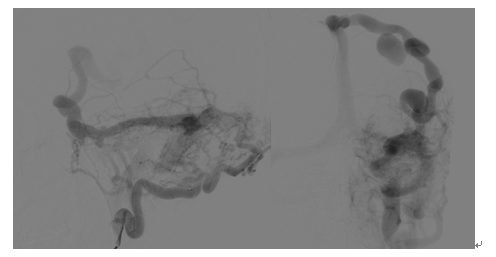

术中造影

该病人是一名42岁的黑龙江籍男性,长期在北京打工,9月1日突发剧烈头痛、右上肢偏瘫,就诊于天坛医院急诊科,行CT检查显示颅内左顶血肿,脑水肿明显;进一步完善CTA发现左侧异常迂曲增粗的巨大静脉及位于血肿中心的巨大球球瘤,双侧头皮颞浅动脉和枕动脉异常增粗,颅底脑膜广泛供血。急诊收入脑血管三病区,考虑脑膜脑动静脉瘘,病情复杂,同时颅内出血量大,颅内血管畸形情况不明确,手术风险极高,拟进一步完善造影检查再行手术治疗,给予脱水保守治疗。入院后第三天早上8时,病人突发意识障碍加重,左侧瞳孔扩大,光反应消失,正在科室讨论病情的赵继宗院士及张东主任医师查看病人,查体后考虑病人发生脑疝,需要急诊手术干预,迅速判断病情后,赵继宗院士和张东主任认为该病人非常适合进入复合手术室进行抢救,随后张东主任团队紧急联系手术室及神经介入科,组织相关医护团队转运病人至复合手术室,以最快的速度开始抢救,经降颅压、气管插管等紧急抢救后病情暂时平稳,病人瞳孔恢复正常。神经介入科杨新建主任团队接到通知后第一时间赶到手术室,首先进行脑血管造影,明确了巨大硬脑膜动静脉瘘的诊断,后使用弹簧圈和血管栓塞剂成功封堵瘘口,明显降低了开颅手术的风险。随后张东主任团队迅速进行开颅手术,在术中B超,和电生理监测下,成功清除脑内血肿,术中发现巨大静脉球瘤为出血责任部位,予以夹闭,同时行去骨瓣减压术,解除脑疝,最终手术历时10小时,顺利结束,病人平稳转运回重症监护病房,苏醒后意识水平及神经功能明显改善。术后经过科室医护团队的精心治疗与护理,病人于9月15日出院,出院时病人神清语利,双侧肢体肌力正常,无明显神经功能障碍,生活完全自理,拟6月后回院行颅骨修补手术。